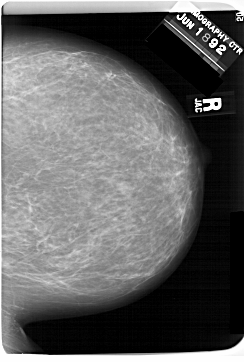

A_1560_1.LEFT_MLO

LEFT_MLO LINES 6346 PIXELS_PER_LINE 5266 BITS_PER_PIXEL 12 RESOLUTION 43.5 OVERLAY